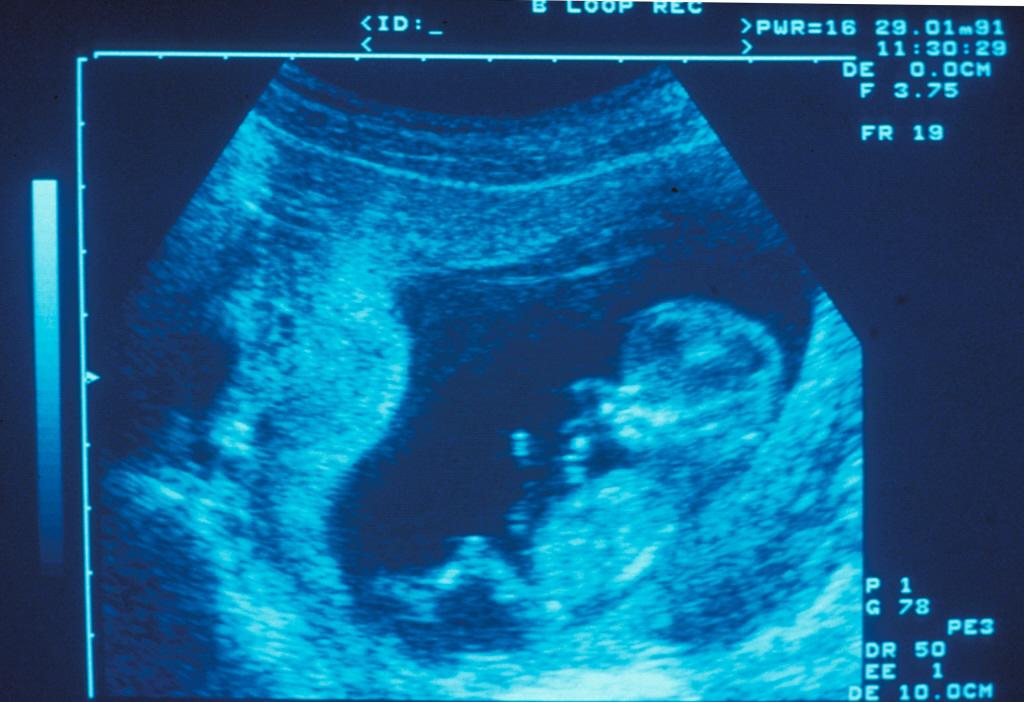

Une greffe in utero de cellules souches hématopoïétiques a été réalisée chez un fœtus atteint de déficit immunitaire combiné sévère lié à l’X, par des équipes du département de biothérapie et de l’unité d’immuno-hématologie pédiatrique de l’hôpital Necker-Enfants malades AP-HP, du département de médecine fœtale de l’hôpital Trousseau AP-HP, de l’Inserm, de l’Institut Imagine, de l’Université Paris Descartes et de Sorbonne université.